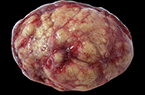

Corps jaune gravidique à 5,5 SA Corps jaune gravide à 5,5 SA Corps jaune gravide à 5,5 SA

Corps jaune gravide à 5 SA Corps jaune gravide à 5 SA Corps jaune gravide à 5 SA